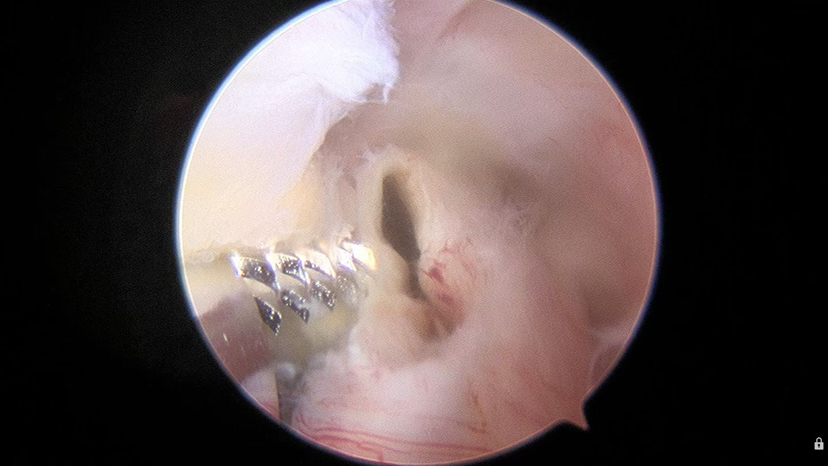

【关节镜手术切除】:无论是否有症状,关节镜手术切除均为主要的治疗方法,创伤小,恢复快!一般认为在不损害交叉韧带功能的前提下,应完整切除囊壁并防止囊液播散,从而达到防止复发的目的。

示例: